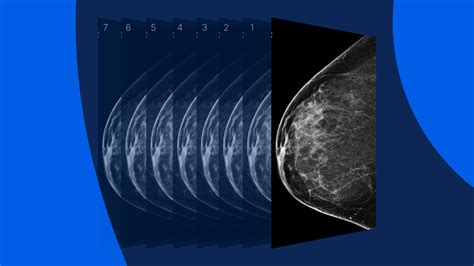

The frequency of your mammograms is just as important as the results themselves. Because normal mammogram images provide a snapshot of your health at a single point in time, regular screenings allow for the monitoring of trends. Yearly or biennial screenings help identify changes that occur slowly over time. If you have a family history of breast cancer or other risk factors, your doctor might recommend starting screenings earlier or increasing the frequency of your appointments.

Staying consistent with your screening schedule ensures that any potential issues are detected at the earliest, most treatable stage. When you view your mammogram as a proactive wellness tool rather than a scary medical procedure, you take an active role in maintaining your long-term health. Remember that the goal of these images is to provide peace of mind and confirm that your breast tissue remains in a stable and healthy state.

⚠️ Note: Always keep your previous mammogram records or know which facility performed them. Radiologists compare your current images to your older ones to spot subtle changes, which is far more effective than looking at one scan in isolation.